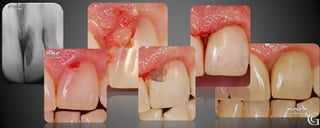

Prótesis Fija Convencional

Restauraciones periféricas totales “coronas”

Las coronas son restauraciones que involucran la totalidad del

diente, confeccionadas fuera de la boca (indirectas totales) que

luego son adheridas al diente en tratamiento. Pueden ser de

diversos materiales, cerámicas, composite y/o metálicas.

Prótesis Fija Convencional Restauracionesperiféricas totales “coronas” Las coronas son restauraciones que involucran la totalidad del diente, confeccionadas fuera de la boca (indirectas totales) que luego son adheridas al diente en tratamiento. Pueden ser de diversos materiales, cerámicas, composite y/o metálicas.